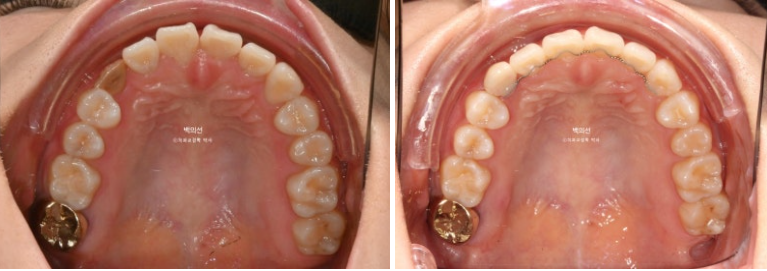

24.10

오래 전 했던 교정으로 어금니 교합은 나쁘지 않은 상태입니다.

인비절라인 라이트로 앞니 배열과 뿌리를 뼛속으로 깊이 넣어주는 치료를 권유드렸습니다.

또한 블랙트라이앵글 사이즈를 줄이기 위한 치간삭제도 계획하기로 했습니다.

25.03

기울어져있던 앞니 치축은 똑바로 개선되었으며 블랙트라이앵글 사이즈는 많이 줄었습니다. 중심선은 아직 개선이 필요합니다.

잇몸퇴축이 있는 위 앞니, 아래앞니 뿌리를 좀 더 안으로 집어넣는 치료계획을 세워 추가장치를 한세트 더 쓰기로 했습니다.